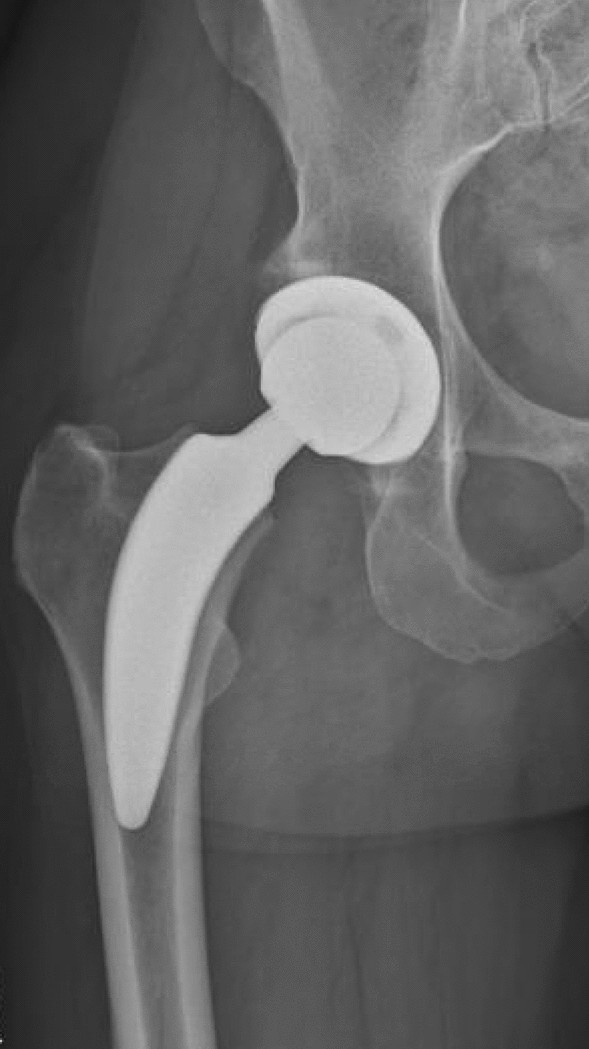

A consecutive series of 254 hips with unilateral index surgery between January 1st 2017 and July 31th 2022 operated by a single surgeon using a MIS direct anterior approach (DAA) to the hip were retrospectively screened for inclusion. The medical records until discharge from hospital were evaluated. In 159 of the cases the Fitmore hip stem (ZimmerBiomet, Warsaw, IN, USA) combined with the Allofit/-S press-fit acetabular cup (ZimmerBiomet, Warsaw, IN, USA) (Group A) and in 95 of the cases the ANA.NOVA proxy hip stem (ImplanTec GmbH, Moedling, Austria) combined with the ANA.NOVA Alpha acetabular cup (ImplanTec GmbH, Moedling, Austria) (Group B) were implanted.

The cementless titanium alloy (TiAl6V4) Fitmore hip stem features a porolock Ti-VPS coating in the proximal part for enhanced bone ingrowth. It is available in four different neck angle options and in 14 different sizes for each offset option2,21. To achieve press-fit fixation, the stem has a triple tapered design. It can be classified as neck-harming short stem according to the recommended level of resection of the femoral neck (Fig. 1)21,22. Reports available in the literature show excellent clinical performance of this stem with high patient satisfaction and high survival rates of 93.7% for revision for all causes and 99.6% for revision due to aseptic loosening at a follow up of 8.6 years2,21,23.

The cementless titanium alloy (TiAl6V4) ANA.NOVA proxy hip stem has a rough titanium plasma coating with electrochemically applied hydroxyapatite (BONIT) to enhance osteointegration. It features a triple tapered design with a calcar guided press fit fixation with a 3-point anchorage with the main fixation zone between medial calcar and lateral cortex. It is available in 12 different sizes with two offset options for each size24. It can be classified as partial femoral neck-sparing short stem according to the recommended level of resection of the femoral neck (Fig. 2)22. Up to date, there are hardly reports regarding the clinical performance and survival rate of this stem. However, it seems to enable satisfying hip geometry restoration and low revision rates due to subsidence at a follow up of 3 years24,25.